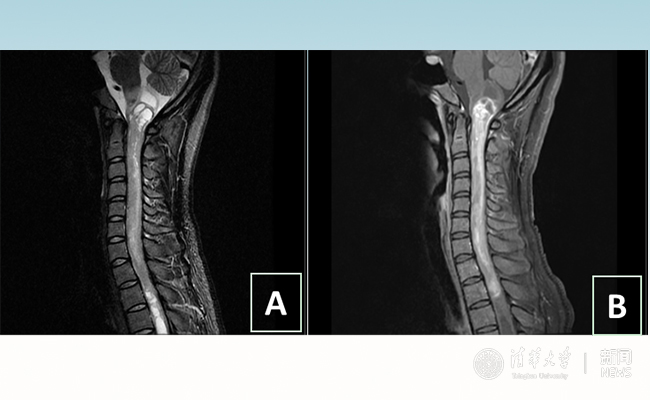

2018.01拯救“90后”女孩 清华长庚神经外科切除20多公分髓内肿瘤

“愿得韶华刹那,开得满树芳华。”27岁的患者小甜(化名)在乐鱼在线平台附属北京清华长庚医院成功进行了手术,神经外科主任王贵怀为其切除了自延髓至胸髓的长达20余公分的脊髓内肿瘤。1月9日,小甜顺利出院,再续芳华!